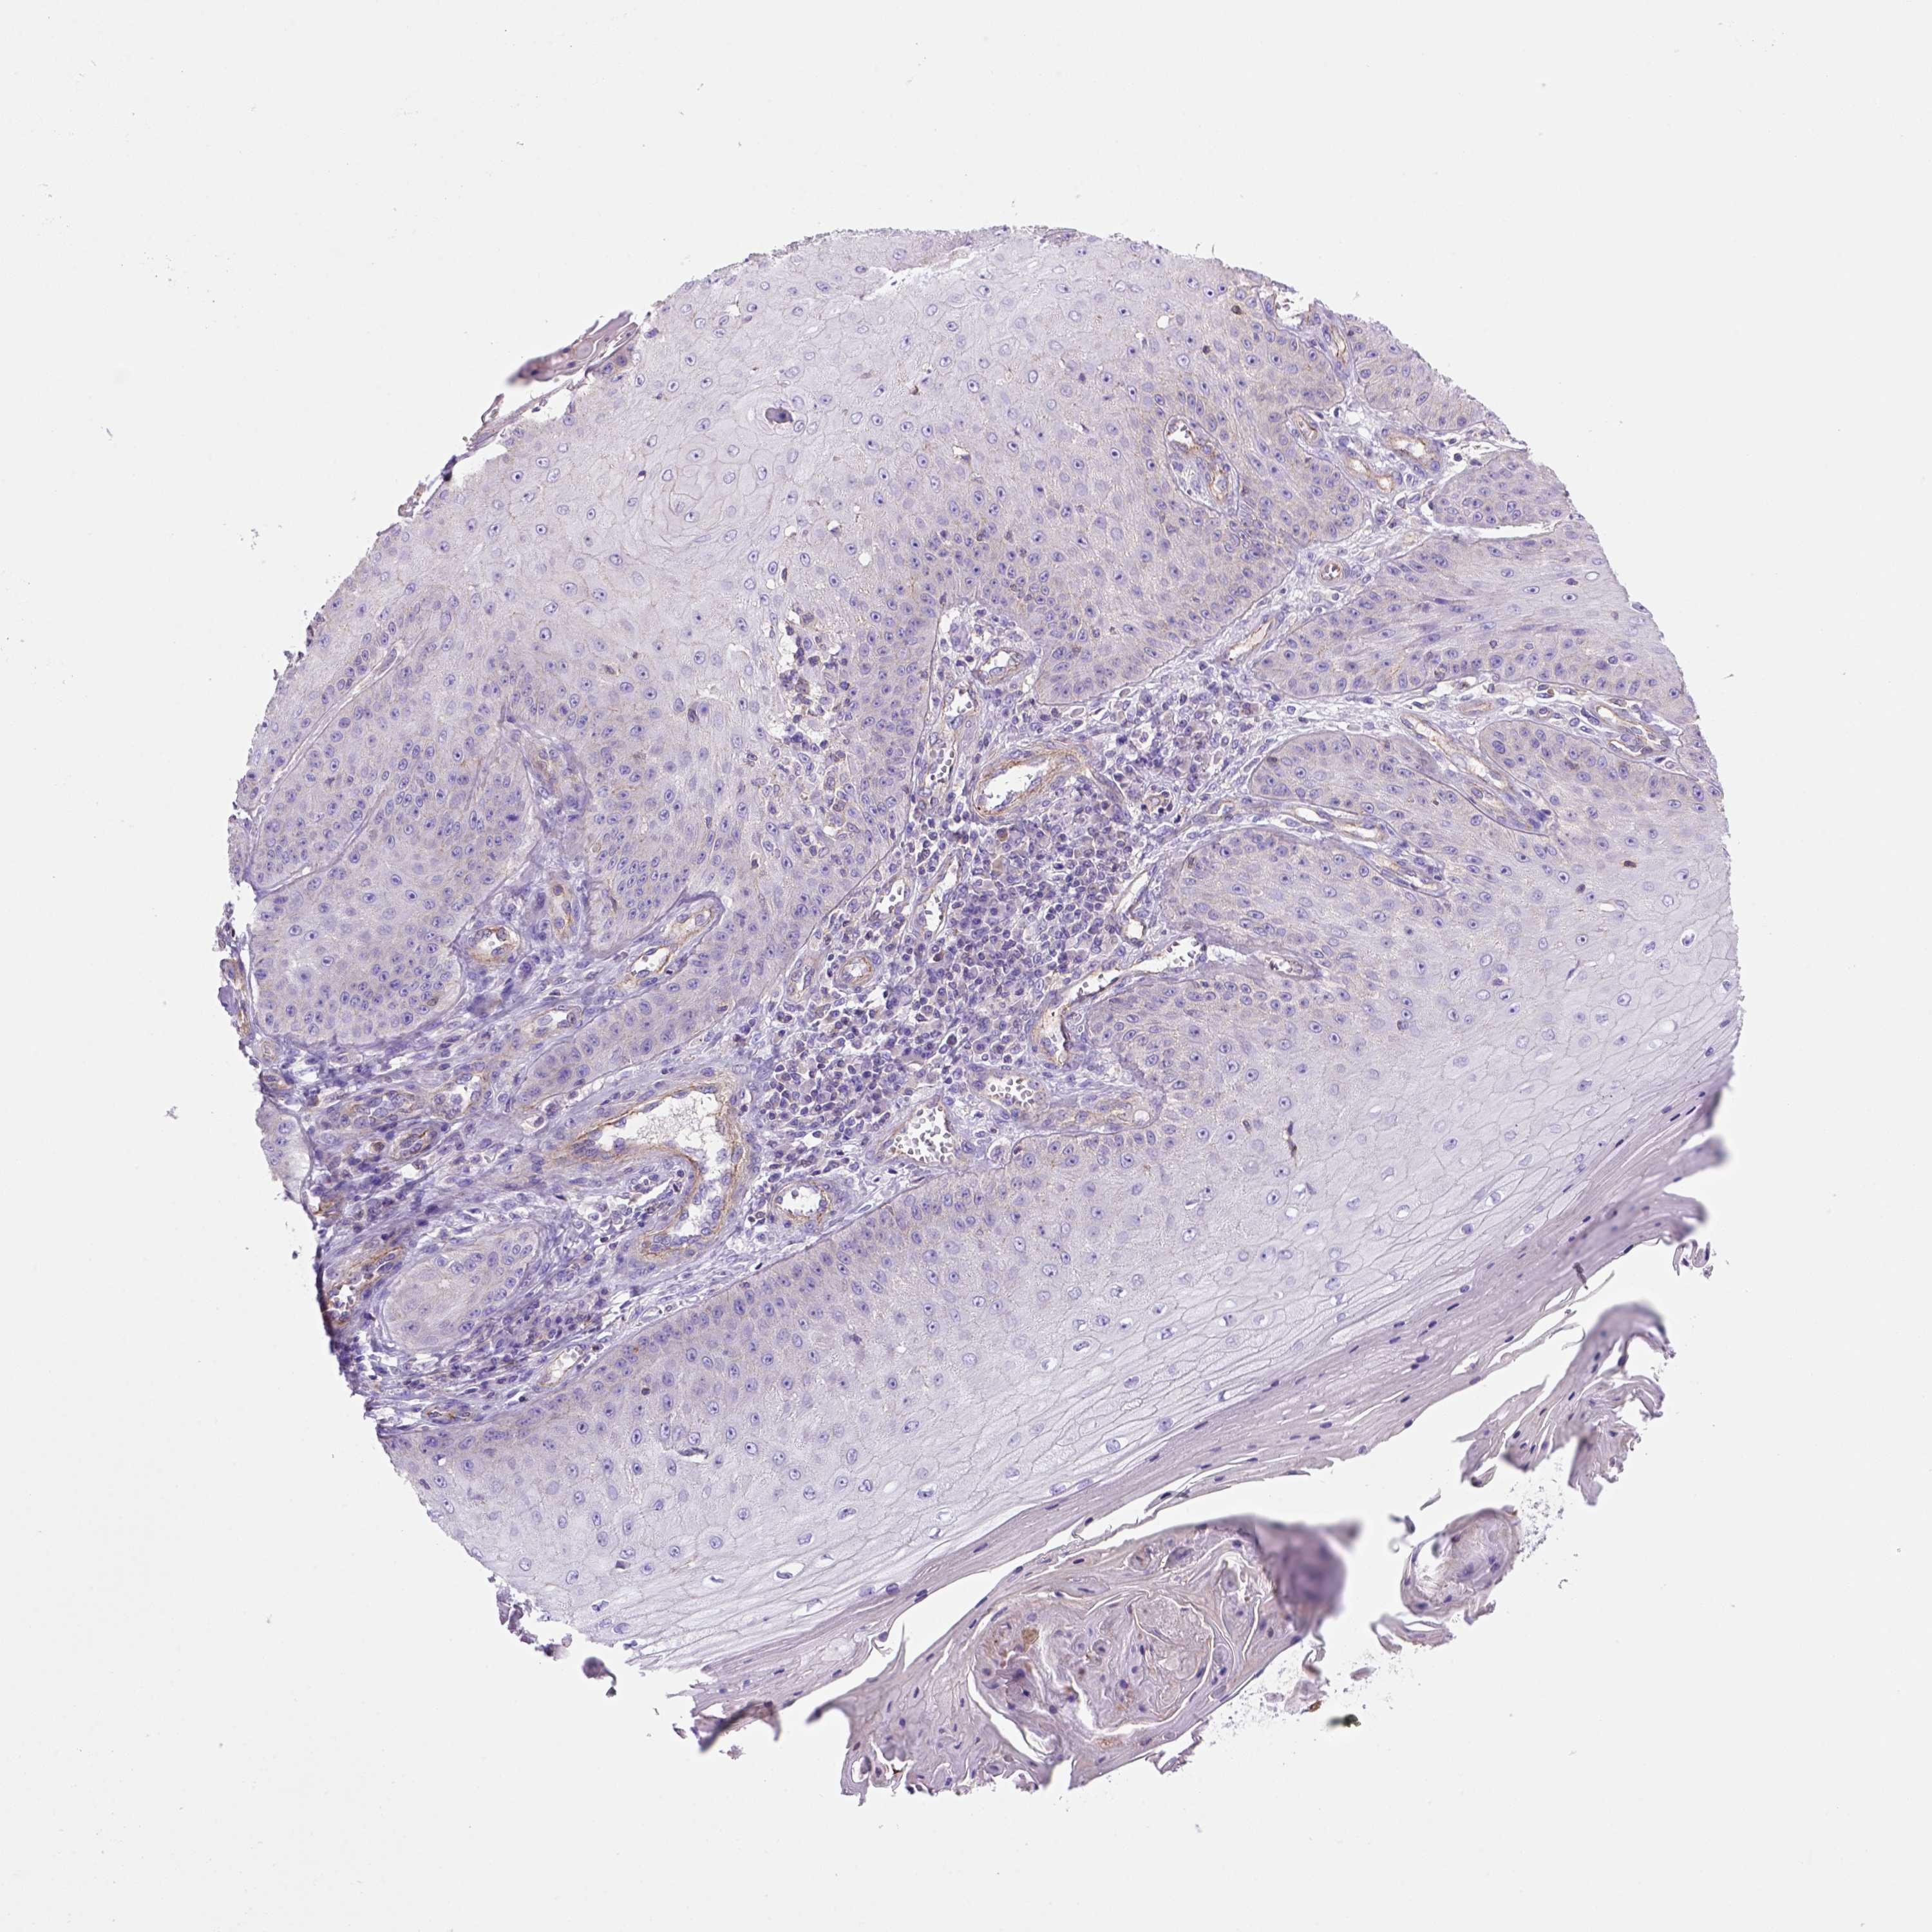

Basal cell and squamous cell cancer

SKIN CANCER - Protein expressioni

A mouse-over function shows sample information and annotation data. Click on an image to view it in a full screen mode. Samples can be filtered based on level of antibody staining by selecting one or several of the following categories: high, medium, low and not detected. The assay and annotation is described here.

Antibody stainingi

Antibody staining in the annotated cell types in the current human tissue is reported as not detected, low, medium, or high, based on conventional immunohistochemistry profiling in selected tissues. This score is based on the combination of the staining intensity and fraction of stained cells.

Each image is clickable and will lead to virtual microscopy that enables deeper exploration of all samples and also displays staining intensity scores, fraction scores and subcellular localization as well as patient and tissue information for each sample.

Antibody HPA069386

Staining

High

Medium

Low

Not detected

Intensity

Strong

Moderate

Weak

Negative

Quantity

>75%

75%-25%

<25%

None

Location

Nuclear

Cytoplasmic/membranous

Cytoplasmic/membranous,nuclear

Basal cell carcinoma

Squamous cell carcinoma, NOS